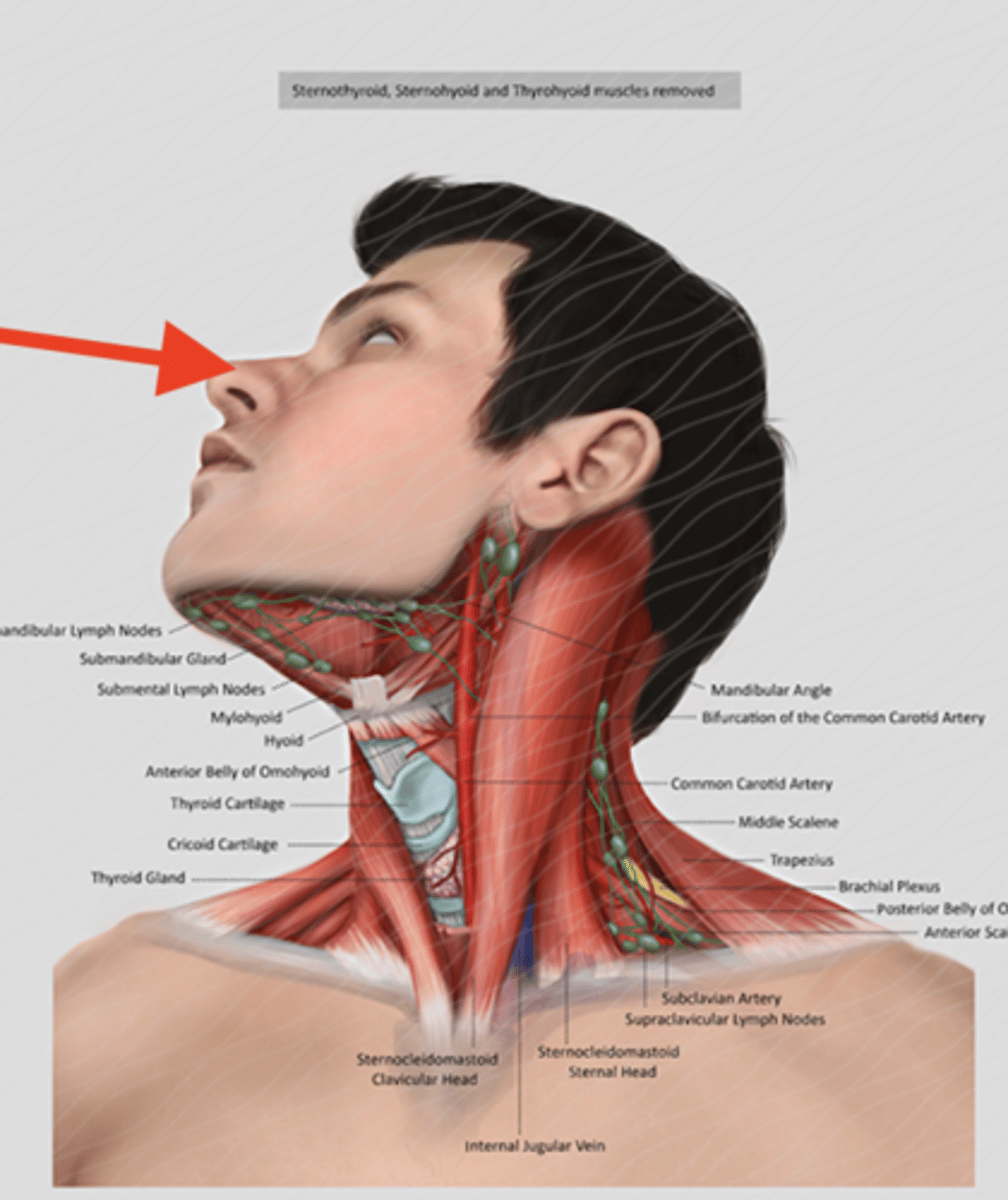

hyoid bone

name the green portion

thyroid cartilage

name the green portion

cricoid cartilage

name the green portion

anterior scalene

middle scalene

posterior scalene

sternocleidomastoid

scalene muscles (surface anatomy)

name these muscles

thyroid cartilage (surface anatomy)

Adam's apple

trachea (surface anatomy)

feel for trachial cartilages